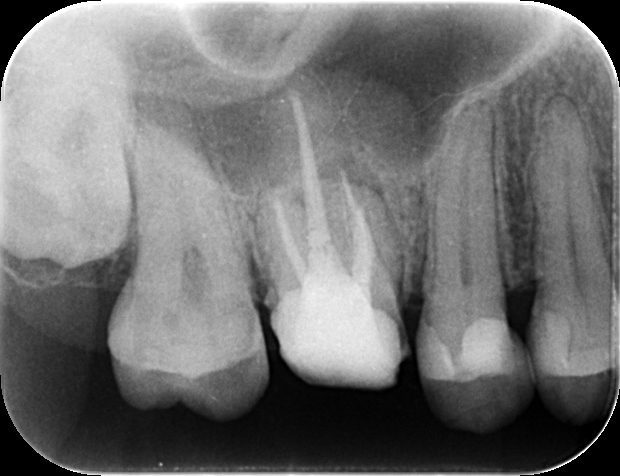

術前レントゲン

術後レントゲン